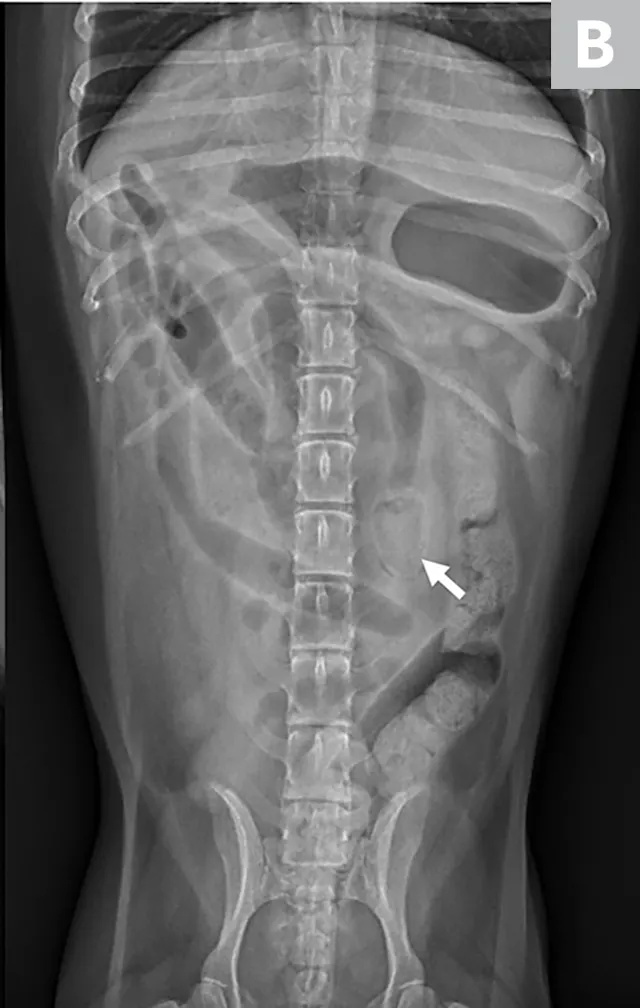

Left lateral image showing segmental dilated gas-filled intestines (dashed arrows) with heterogeneous soft tissue in a small intestinal segment (solid arrow) in a dog. The foreign material was cloth, and the diagnosis was small intestinal mechanical obstruction. Exploratory laparotomy was performed.